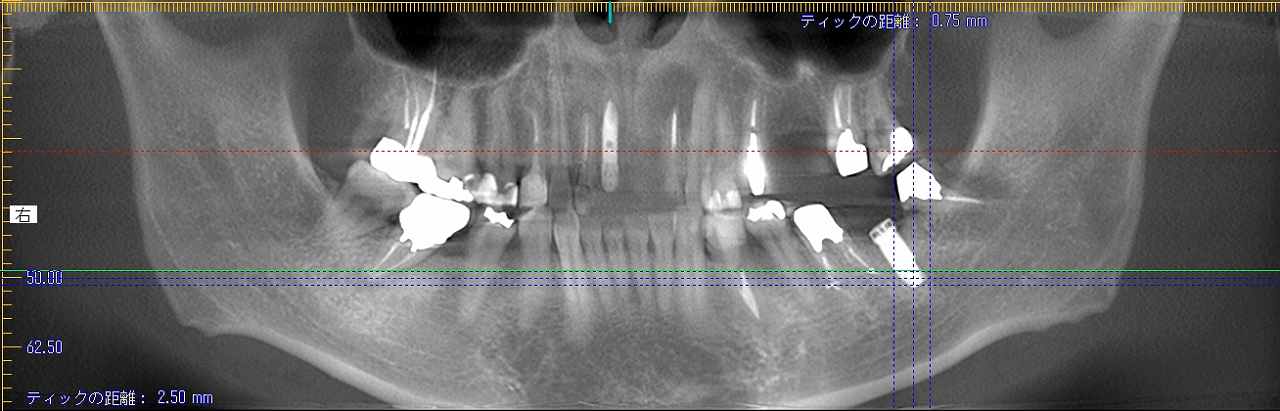

左下のインプラント埋入 支台歯となる歯が弱いとブリッジにならないこともあります

左下のインプラント埋入 支台歯となる歯が弱いとブリッジにならないこともあります

左下7番のインプラント早期埋入のために抜歯していきます

2か月待ちました

インプラント埋入になります

骨欠損が大きくGBRしていきます

下顎7番のインプラント埋入は下顎管とも近くなり、難しさはあります